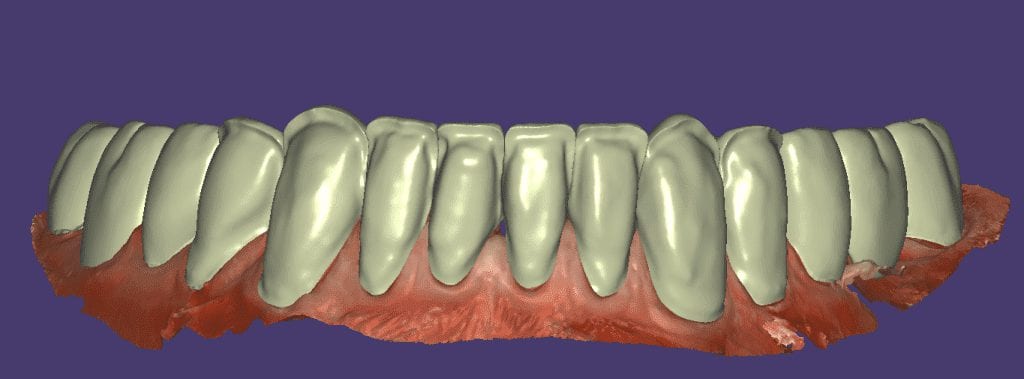

The digital models were then imported into a third party software where a library of tooth morphologies are available for the clinician to choose from.

Once the appropriate library is chosen, the digital wax ups are performed. In the subsequent photos you can see the transparent overlay of the wax-ups to the original position of the existing dentition

Once the case is designed to the ideal vertical dimension then multiple shells can be fabricated for treatment. The wax up model can be uniformly reduced by .5mmm’s circumferentially and a temporary shell can be designed. Once the teeth are prepared, these shells can be relined and seated onto the preps.

Over the course of a few appointments, the vertical dimension was reduced and the temporaries were adjusted to the patient’s desires. The new upper and lower arch were captured with the Medit i500 and the jaws were related to each other.